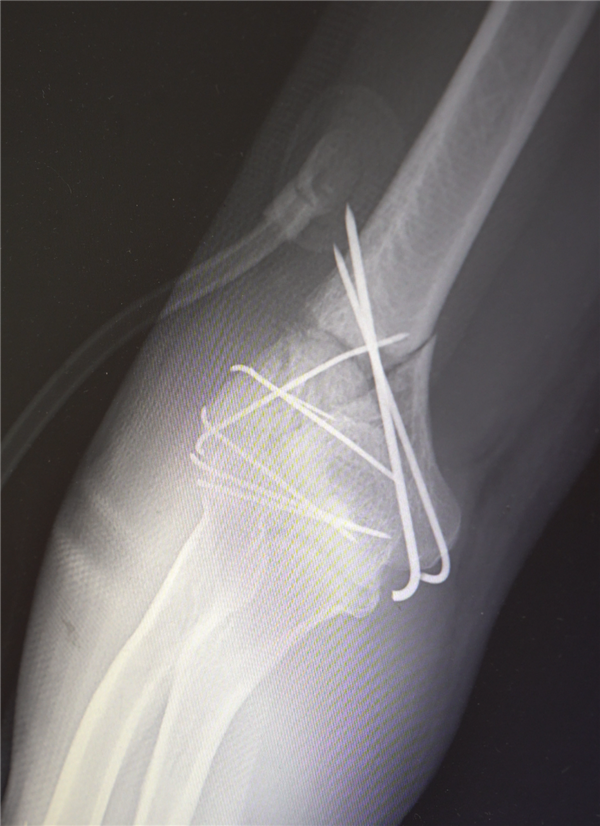

鉴于男子多处骨折,其中最严重的当属右肘部C3型粉碎性骨折,关节面及髁上严重粉碎(碎成了七块),肘关节易粘连,复位固定难度极高。

最终医疗团队采用了“拼古董”式复位固定技术,就像修复一件珍贵的古董瓷器,先拼接大块骨块再贴合小块,先后进行了两次手术。